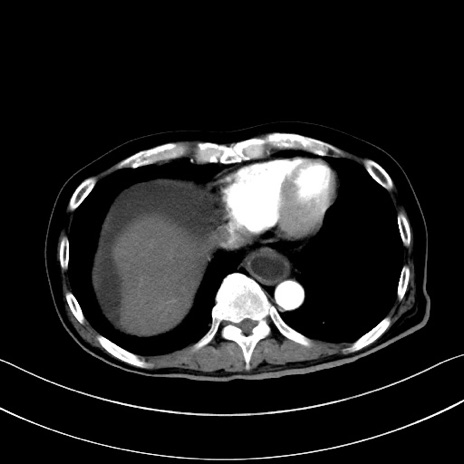

症例28(横断像)

【症例】60歳代男性

【主訴】嘔吐

【現病歴】胃癌にて胃全摘後。食思不振が悪化し、夜中に嘔吐することがある。

【既往歴】胃癌、胃全摘、脾摘、胆摘後

【データ】WBC 5900、CRP 10.56